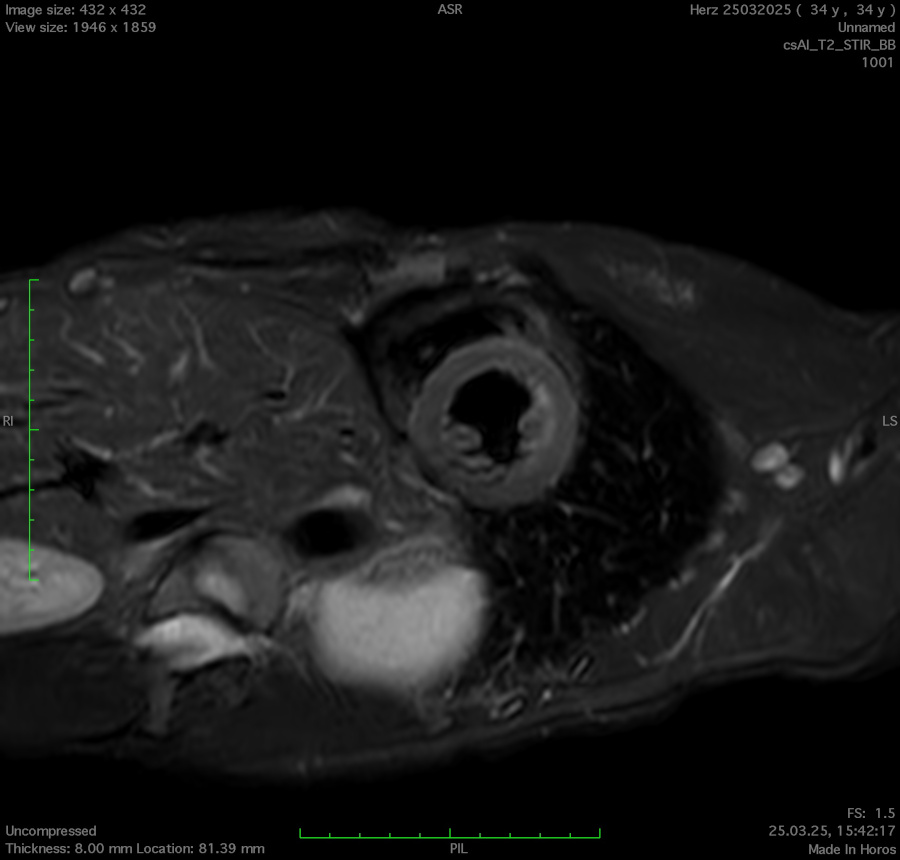

MR Cardio Narbendarstellung (PSIR Black Blood)